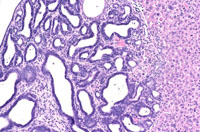

Because their occurrence is rare, morphological characteristics of cholangiomas are not well characterized and must be distinguished from biliary cysts. Cholangiomas are discrete nodular growths in which the proliferating biliary structures are lined by a single layer of relatively uniform cuboidal epithelium. A discrete cholangioma protruding above the natural surface of the liver.

Neoplasm is comprised of large acini lined by cuboidal epithelium with occasional papillary projections into the lumen.

This cholangioma has connective tissue stroma between acini. Higher magnification shows acini lined by tall cuboidal epithelium. The nuclear crowding and occasional nests of epithelial cells in the stroma suggests progression toward malignancy.